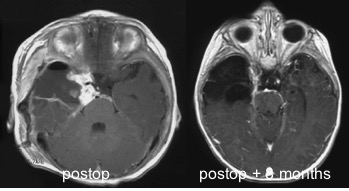

macroscopiquement, la tumeur a le plus souvent une attache méningée, et elle est d’emblée apparente à l’ouverture durale. elle est de consistance ferme, avec un fort contingent kystique ; elle se clive relativement bien des structures cérébrales et vasculaires adjacentes. lors des récidives cependant, elle peut adhérer intimement aux vaisseaux du polygone de willis et infiltrer le cortex et les ventricules.

il repose avant tout sur la chirurgie, qui est souvent urgente voire extrêmement urgente. le rôle des chimiothérapies (de type LGG) n’est pas établi avec certitude en raison de la rareté des cas de récidive.